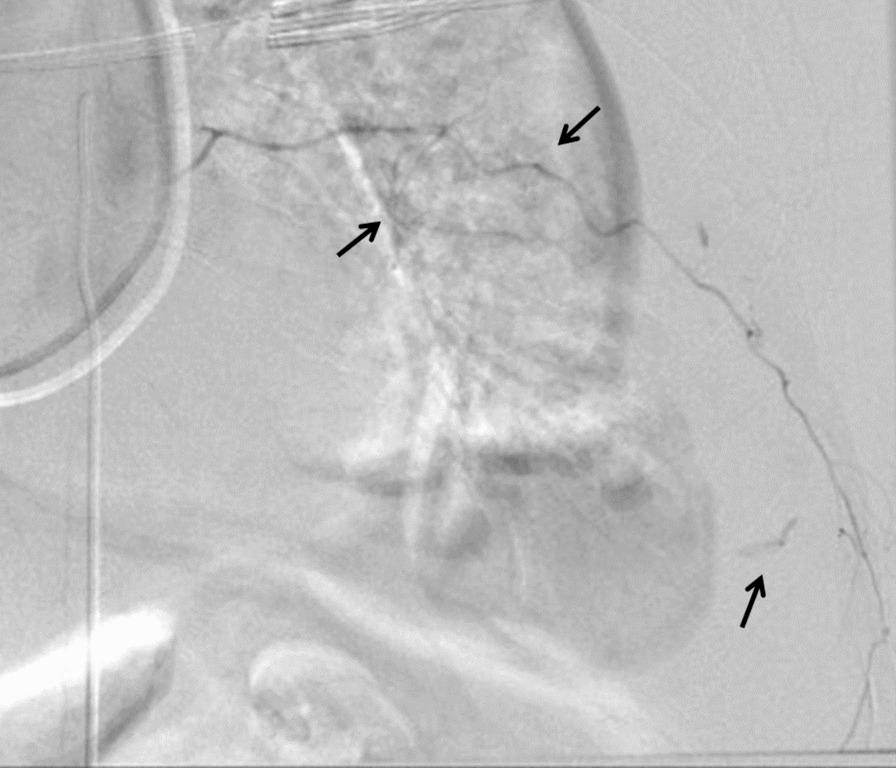

A 63-year-old Japanese man was admitted to the emergency department owing to sudden chest and back pain, dizziness, and nausea. Emergency coronary angiography revealed myocardial infarction secondary to right coronary artery occlusion. After intra-aortic balloon pumping, percutaneous coronary intervention was performed in the right coronary artery. At 12 hours following percutaneous coronary intervention, the patient developed new-onset left anterior chest pain and hypotension. Contrast-enhanced computed tomography revealed 15 sites of contrast extravasation within a massive left extrapleural hematoma. Emergency angiography revealed contrast leakage in the left 6th to 11th intercostal arteries; hence, transcatheter arterial embolization was performed. At 2 days after transcatheter arterial embolization, his blood pressure subsequently decreased, and contrast-enhanced computed tomography revealed the re-enlargement of extrapleural hematoma with multiple sites of contrast extravasation. Emergency surgery was performed owing to persistent bleeding. No active arterial hemorrhage was observed intraoperatively. Bleeding was observed in various areas of the chest wall, and an oxidized cellulose membrane was applied following ablation and hemostasis. The postoperative course was uneventful.

一名 63 岁的日本男性因突发胸痛、背痛、头晕和恶心而被收入急诊部。紧急冠状动脉造影显示右冠状动脉闭塞引起的心肌梗死。在主动脉内球囊泵后,对右冠状动脉进行了经皮冠状动脉介入治疗。在经皮冠状动脉介入治疗后 12 小时,患者出现新发左前胸疼痛和低血压。增强 CT 显示巨大左胸外血肿内有 15 个造影剂外渗部位。紧急血管造影显示左第 6 至 11 肋间动脉有造影剂渗漏;因此,进行了经导管动脉栓塞术。在经导管动脉栓塞术后 2 天,他的血压随后下降,增强 CT 显示胸外血肿再次扩大,有多个造影剂外渗部位。由于持续出血,进行了紧急手术。术中未观察到活跃的动脉出血。在胸腔壁的各个部位观察到出血,并在消融和止血后应用氧化纤维素膜。术后过程平稳。